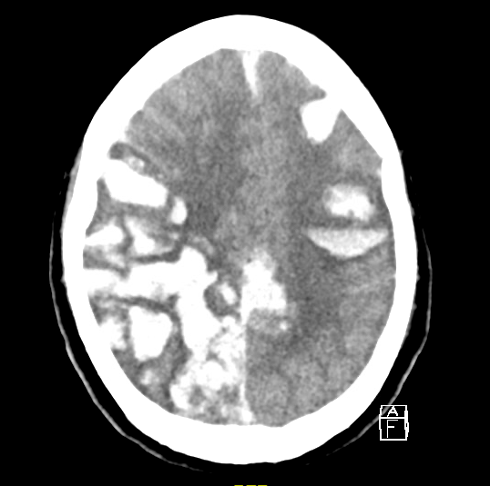

Case 3: A 59-year-old female on apixaban presents after sustaining a head injury. CT shows the following. What is the diagnosis?

Figure 8. Case 3’s CT scan of the head. Image courtesy of the Baylor Scott and White Memorial Hospital–Temple, Texas.

Answer: Intraparenchymal hematoma with intraventricular extension